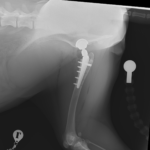

術後X線評価ではインプラント設置は良好。

カップは寛骨臼内側壁に適切に接触し、前後柱間で良好に中心化されています。

ステムは髄腔中央に位置し、内側皮質との接触も良好です。インターロッキングスクリュー固定も適切で、安定した初期固定強度が得られています。

Angle of Lateral Opening (ALO):約45°

Retroversion:約30°

True stem anteversion:約25°